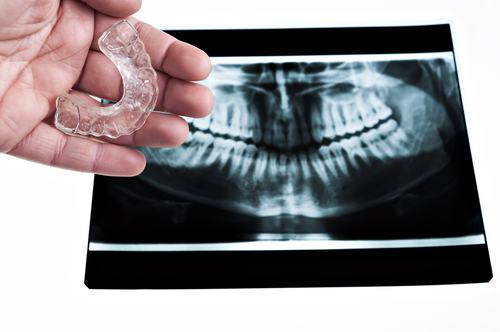

Vous pouvez recourir à l’utilisation de protège-dents (attelles). Ils protègent les dents des pressions exercées par le fait de serrer ou grincer des dents.